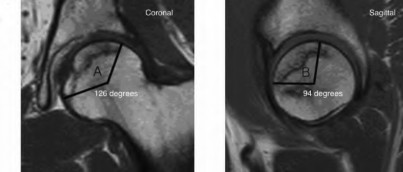

A 72-year-old female presents with progressive left thigh and knee pain for the last year. 5 years ago she sustained a femoral neck fracture treated with the implant seen in Figures A-C (current radiographs). The thigh pain is worse with weight-bearing. C-reactive

protein and erythrocyte sedimentation levels are within defined limits. Which of the following is the most likely cause of her pain?